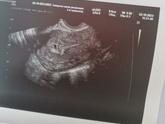

Прошла второй скрининг и расстроилась

Приклеплю фото. Узист смотрел меня минут 40, Крутил то на левый то на правый бок, смотрел кровотоки. Итого плохой кровоток в пуповине. Развитие ребёнка … Читать далее